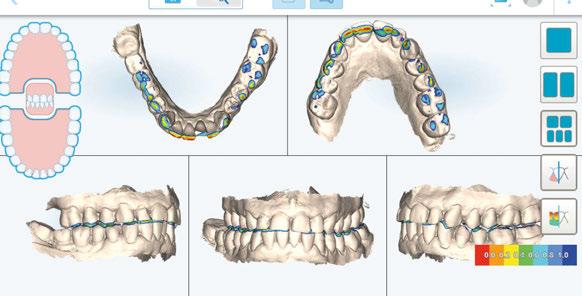

-Protocolo de planificación digital del caso mediante RealGUIDE® (STL+DICOM) (Figura 4) (Cuadro 1).

Figura 4. Planificación digital mediante RealGUIDE.

A continuación, para la planificación de los implantes dentales y el diseño de la férula de cirugía guiada se usó la plataforma digital RealGUIDE®. Para ello se realizó el matching, por un lado, del archivo STL del encerado digital; y, por otro, del archivo 3D. De esta manera, se pudo analizar el tejido óseo residual apical a cada diente y la posición de la raíz respecto a las corticales vestibular y palatina. También se estudió la relación de los contornos óseos con los tejidos blandos y con la posición final de los márgenes cervicales de la restauración protésica, pudiendo así planificar la posición 3D correcta de los implantes. En esta primera fase se diseñó una férula quirúrgica para la elevación de seno bilateral a partir del software RealGUIDE™, que nos sirvió de guía para el diseño de las ventanas de acceso. Esta férula se imprimió con la impresora 3D Formlabs® (Figura 7)